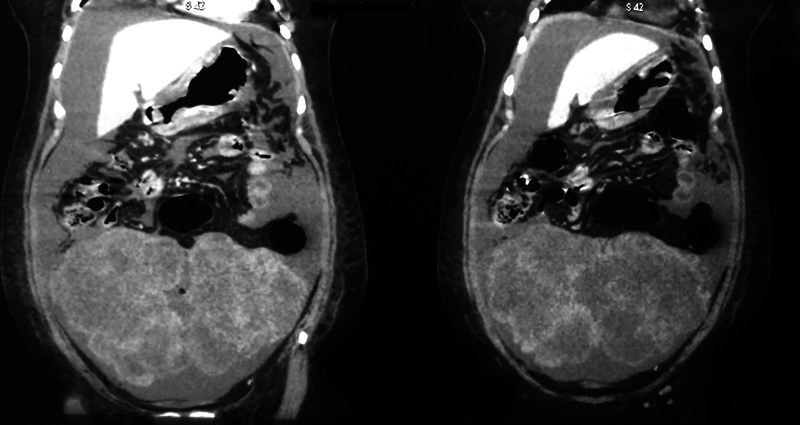

Abstract Image